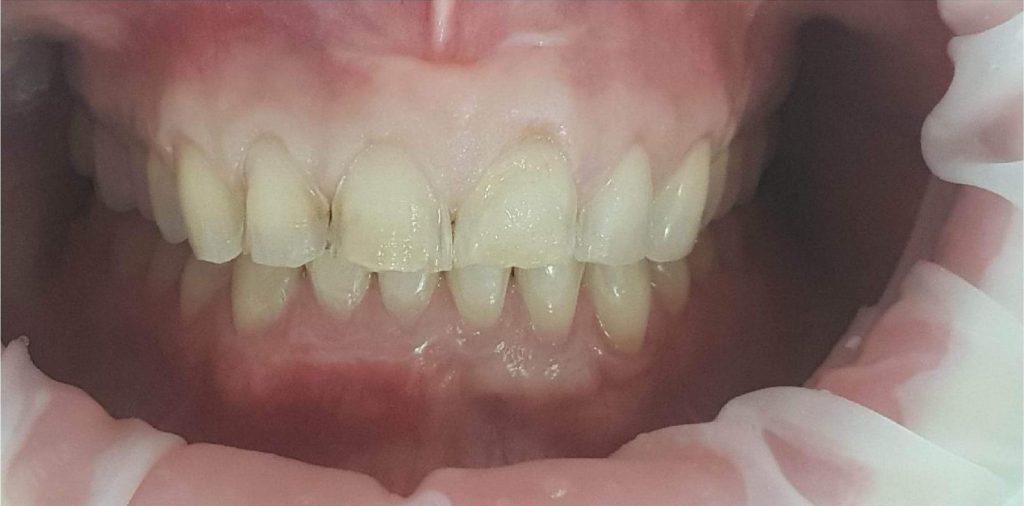

Pierwszy etap to kompleksowa konsultacja u dr Joanny Zawirskiej-Poły. Podczas tej wizyty zostało wykonane badanie przedmiotowe, podmiotowe, badanie mięśni i stawów, analiza okluzji, badanie stomatologiczne, tomografia komputerowa, rejestracja fotograficzna i długa rozmowa z Pacjentką na temat jej oczekiwań.

Pacjentka, zgłaszając się już na kolejną wizytę świadomie podjęła opcję pośrednią z proponowanych działań: wyleczenie zębów zachowawczo, endodontycznie z zabezpieczeniem protetycznym, estetyczne korekty uśmiechu licówkami, ćwierćkoronami i koronami, jednak bez pełnej przebudowy zwarcia (z zachowaniem starszych odbudów w strefach bocznych, które były wykonane na implantach w przeszłości), która jest zawsze najbardziej polecana, odtwarza prawidłowe kontakty, a także umożliwia lekarzowi i technikowi najlepsze warunki do nadania odpowiednich i harmonijnych kształtów. Te wszystkie działania chronią na przyszłość staw skroniowo-żuchwowy.

Pomimo zaleceń dr do wdrożenia również leczenia ortodontycznego, Pacjentka, znając wszystkie wady i zalety bezwzględnie zdecydowana zakamuflować stłoczenia, nieprawidłowości kontaktów, płaszczyzny zgryzowe, tylko i wyłącznie protetycznymi rozwiązaniami. Dr Joanna ustaliła z Pacjentką pod Jej wymagania wspólny plan działań. Wybierając takie rozwiązanie lekarz i laboratorium ma zawsze utrudnienie, by jaknajbardziej harmonijnie zaplanować projekt uśmiechu.